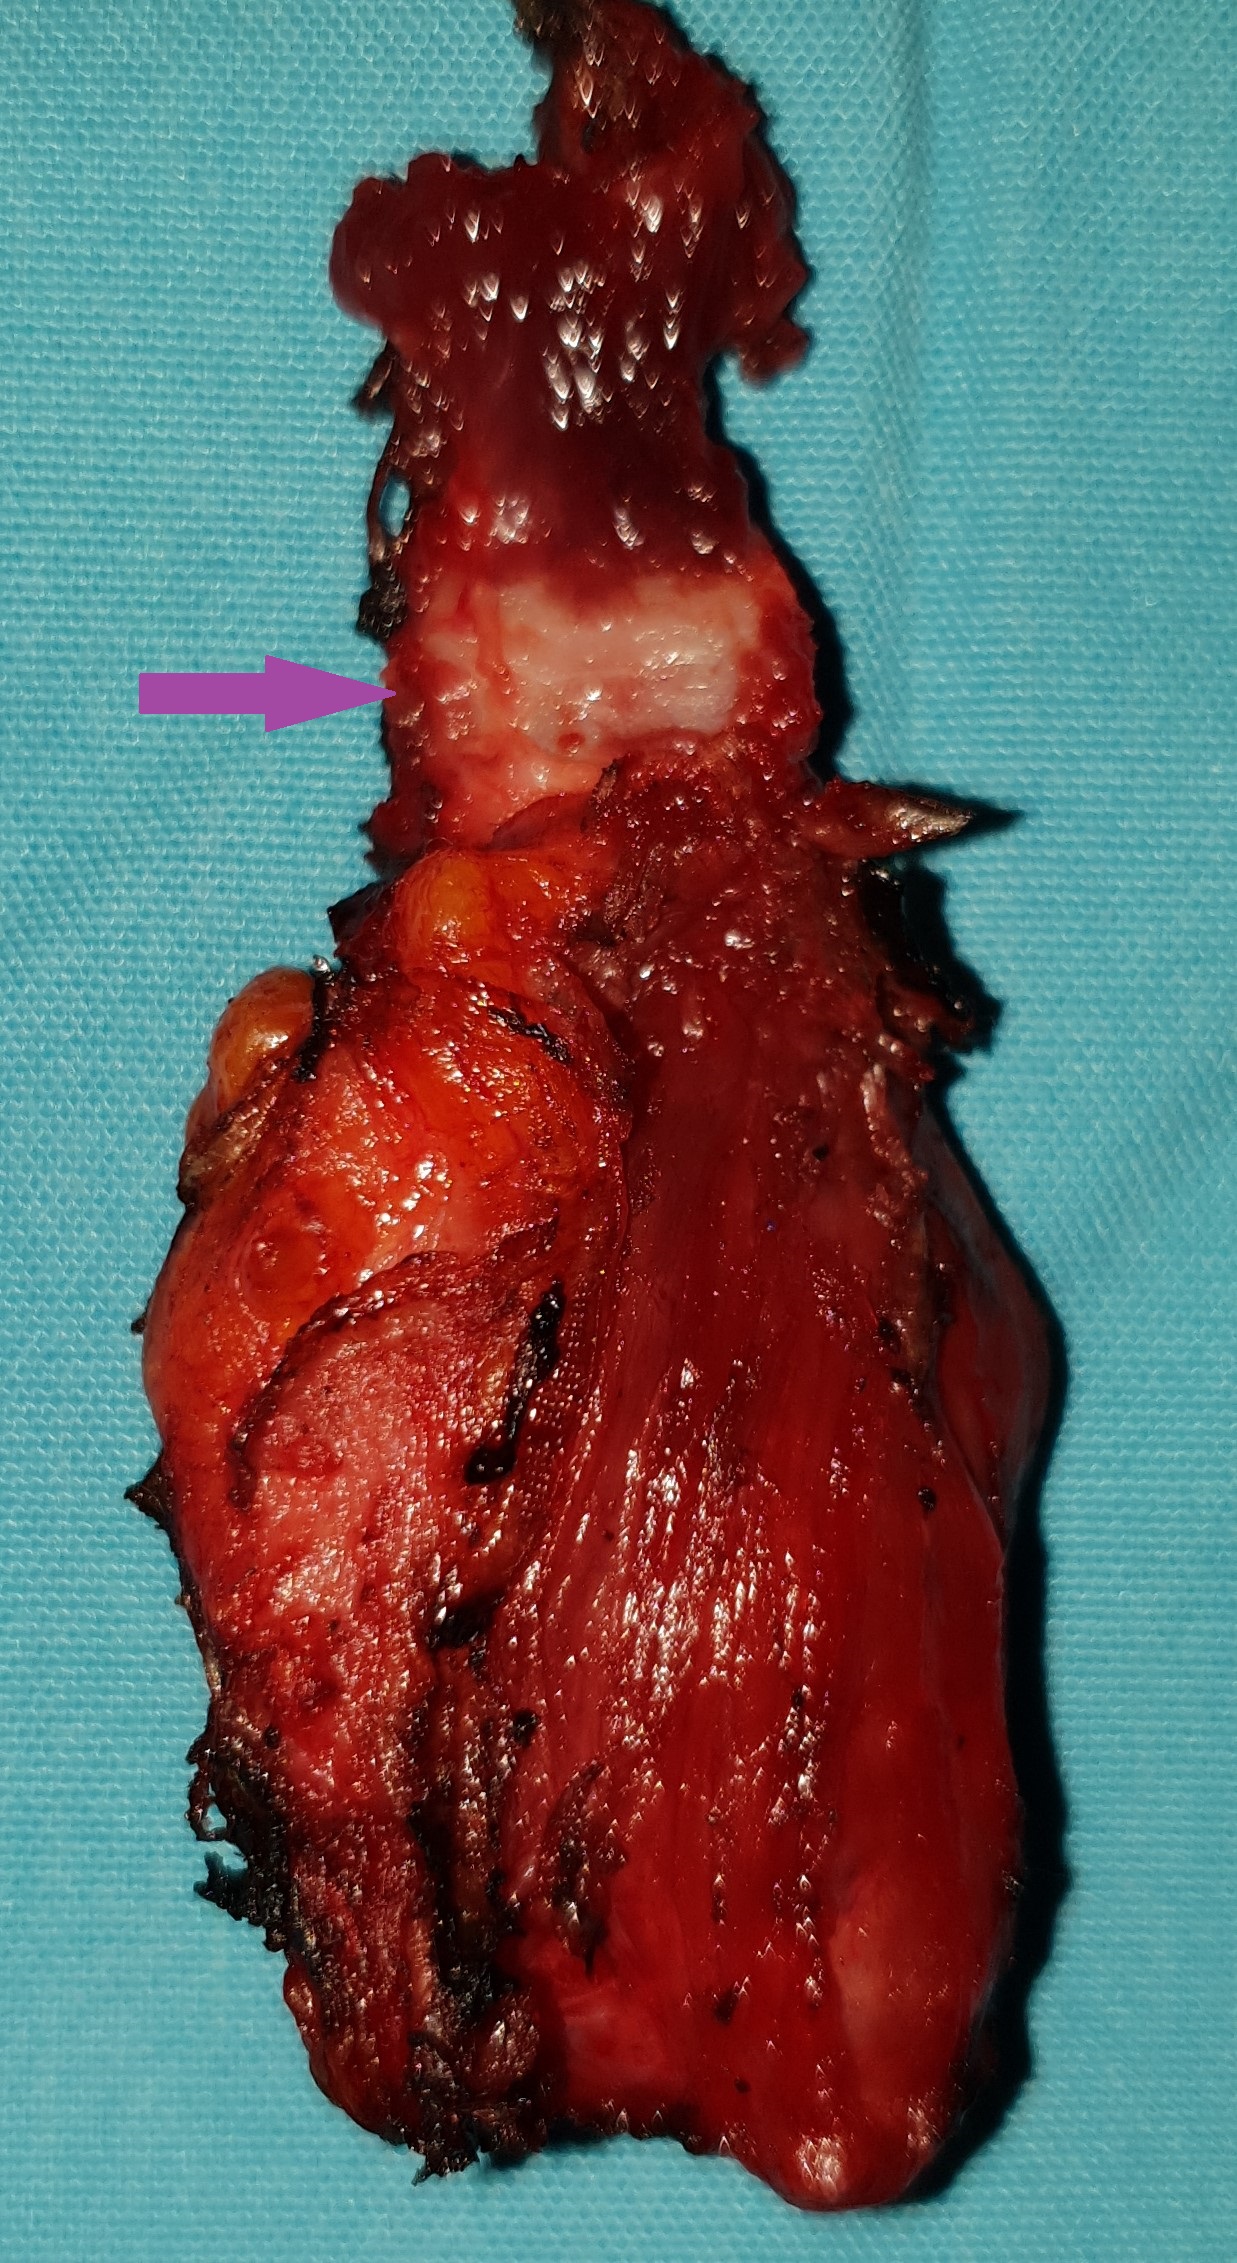

Gross examination of the excised cyst reveals a smooth surface lining of uniform thickness without papillary projections (Courtesy Dr. V. Penopoulos)